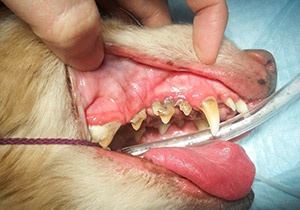

歯石除去・スケーリングなど

ワンちゃん、猫ちゃんに歯ブラシ…最近は動物を飼う方の知識も向上してきて、歯のケアを行う飼い主さんは増えてきています。その一方で、ワンちゃん、猫ちゃんに歯ブラシ!とびっくりされる方もおります。野生動物は歯ブラシなんてしないのだから…と思う方もいらっしゃるみたいですが、ご自分のワンちゃん・猫ちゃんの口の中、見てみてください。歯石がこびりついている、口臭がする…といったことは結構あります。ワンちゃん猫ちゃんの口腔内はアルカリ性のため、弱酸性のヒトの口腔内と比べ歯垢が歯石に変化しやすいのです。ヒトでは虫歯が多いですが、ワンちゃん猫ちゃんの場合、虫歯は比較的少なく、歯周病がとても多いのです。歯石は細菌と唾液の塊の為、口臭や見た目の問題だけではなく、心臓や肝臓、腎臓など体全体へも悪影響を及ぼすことがありますから、たかが歯周病とは言っていられません。

歯周病が進行すると、歯肉炎が生じます。また、歯肉が徐々に下がります。敏感な子の場合、口を痛がる、硬いものを食べたがらないなどの症状がみられることもあります。やがて歯の根っこに膿がたまっていき、歯根周囲病巣を引き起こします。歯根部にはスペースがあまりないので、この膿が溜まりすぎると、やがて皮膚を突き破って外側に漏出します。この段階になると、眼の下が急に腫れたり、突然穴があいて膿が漏れ出し、出血したりします。また、上顎の場合歯の根っこのすぐ上側は鼻腔ですので、鼻腔内で膿が出ると鼻出血などの症状となります。

超音波スケーラーという器具を使い、歯にこびりついた歯石を除去します。歯石はこれできれいにできますが、このままだと歯の表面に細かいざらつきが残り、歯石がつきやすくなってしまうので、ポリッシング剤(研磨剤)というものを二種類使い、歯の表面を滑らかにして再度の歯石の付着を予防します。同時に、長年の歯石付着による炎症で、歯肉がかなり下がってしまい、歯石を除去してしまうと歯がぐらぐらな場合や、歯根に膿がたまってトラブルを抱えている場合は、抜歯も同時に行うことがあります。